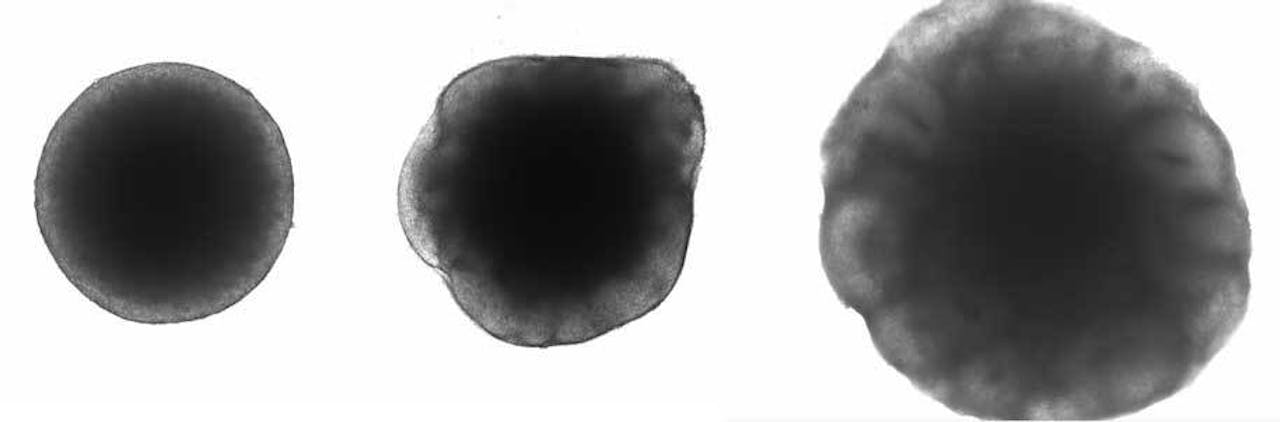

V.l.n.r. Een embryoid body na zes dagen in het medium, na twaalf dagen in het medium (met lichte neuronale stamcellen aan de buitenkant), en een organoïde van twintig dagen oud met ventrikels aan de buitenkant.

Joery den HoedIn een echt embryonaal brein ligt echter vast in welke richting de neuronen zich ontwikkelen. Zo ontstaat er elke keer weer een brein dat ongeveer op dezelfde manier georganiseerd is en er hetzelfde uitziet. “Bij een organoïde heb je geen controle over de vorm. Elk organoïde heeft meerdere ventrikels, maar die zitten nooit op precies dezelfde plek en zijn niet van dezelfde grootte. De processen die binnen zo’n ventrikel plaatsvinden zijn echter wel vergelijkbaar met die in een ontwikkelend embryo.” Zo zien de onderzoekers toch hoe specifieke genen bijdragen aan die ontwikkeling.